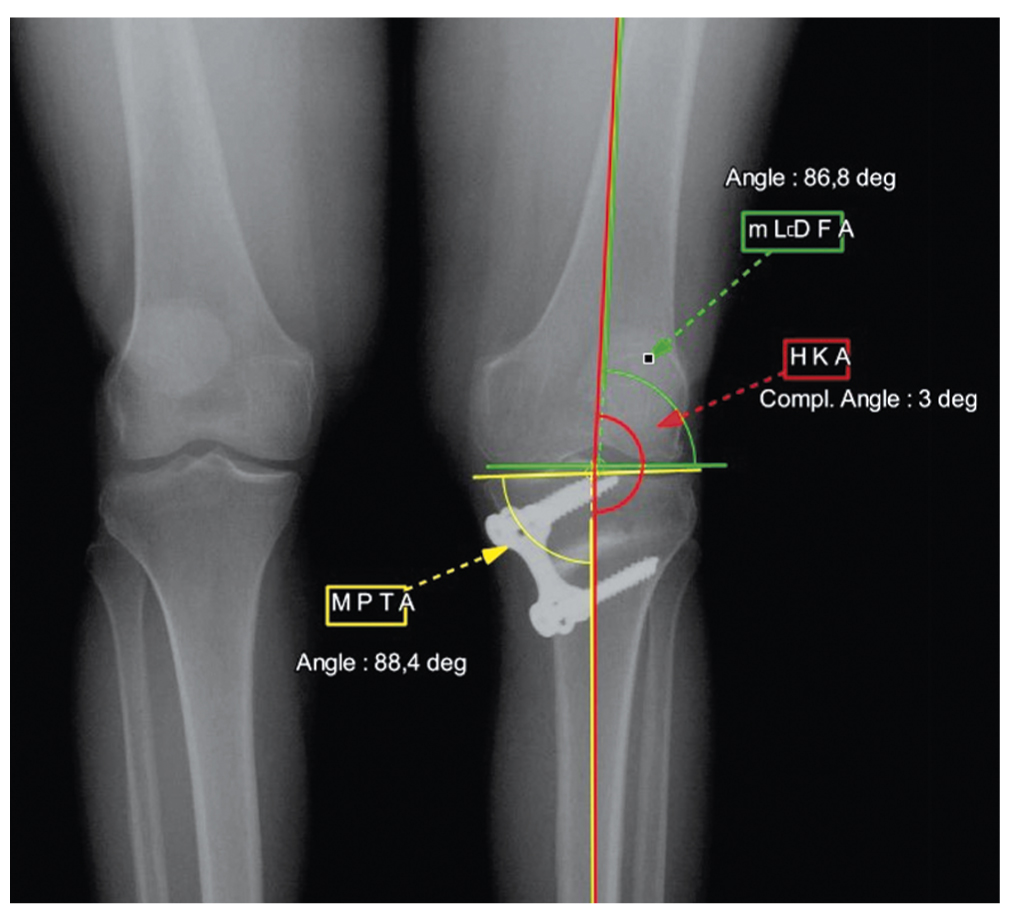

Инструментальная диагностика включала магнитно-резонансную томографию и рентгенографию нижних конечностей на протяжении с нагрузкой собственного веса тела. На первичных топограммах отмечена II стадия остеоартроза медиального компартмента коленного сустава по классификации Ahlbäck. Механическая ось нижней конечности приходилась на край медиального мыщелка большеберцовой кости левого коленного сустава, т.е. смещение механической оси было выше нормы, а значение механического угла между бедром и большеберцовой костью составляло 10° варуса (hip-knee-ankle angle, HKA) (рис. 1).

Рис. 1. Топограмма нижних конечностей до первичной остеотомии. / Fig. 1. A topogram of the lower extremities before the primary osteotomy.

Референтное значение механического медиального проксимального большеберцового угла (medial proximal tibial angle, MPTA) составило 84,7°, механического латерального дистального бедренного угла (mechanical lateral distal femoral angle, mLDFA) — 87° (см. рис. 1). По данным магнитно-резонансной томографии повреждение хряща медиального компартмента классифицировалось как IV степень по Outerbridge (1961). Наблюдалось также комбинированное повреждение тела и заднего рога медиального мениска.